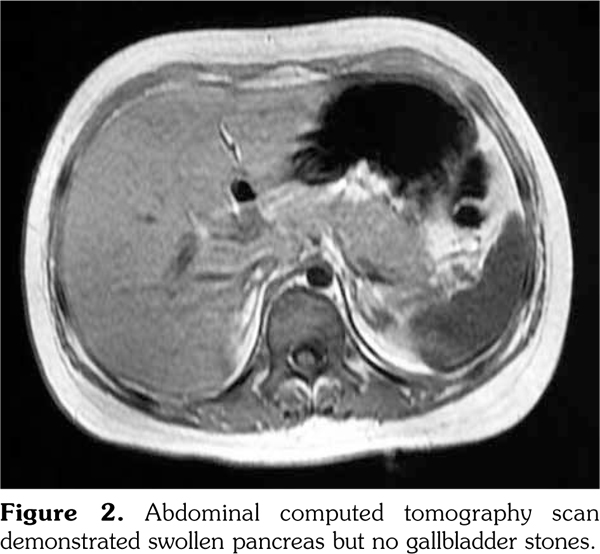

An 11-year-old girl was admitted to our department with a six-month history of anorexia and rashes on her face and extremities (Figure 1). On admission, her axillary temperature was 37.7°C, heart rate was 130 beats/minute, blood pressure was 82/47 mmHg, respiratory rate was 22 breaths/minute, and oxygen saturation was 95%. Cardiac examination revealed a soft systolic murmur at the apex with low heart sounds. She had malar rash, discoid rash, hepatosplenomegaly, and edema of the lower extremities. The subsequent autoimmune and serologic workup came back positive for anti- nuclear antibody at a titer of 1:3200, positive anti- double stranded deoxyribonucleic acid, anti-Smith antibody, and low complements (0.28 g/L) and complement 4 (C4) (0.03 g/L). Other laboratory studies exhibited anemia (red blood cell 3.1∞1012/L, hemoglobin 99 g/L), proteinuria (24-hour urine protein 300 mg/day), elevation of acute-phase reactants (C-reactive protein 132 mg/L, erythrocyte sedimentation rate 54 mm/hour), hyperamylasemia (208 units/L), hyperlipasemia (1556 units/L), and raised creatine kinase (CK, 375 units/L) and CK-MB (83 units/L). Electrocardiogram revealed sinus tachycardia with T wave inversion. Echocardiography showed normal left ventricular size but global hypokinesia with an ejection fraction of 37%. Abdominal computed tomography demonstrated swollen pancreas but no gallbladder stones (Figure 2). Renal biopsy revealed diffuse proliferative glomerulonephritis Class IV-G. Our patient was diagnosed as having systemic lupus erythematous (SLE) complicated by pancreatitis and myocarditis. SLE disease activity index score was 24. She was treated with a course of pulse methylprednisolone 10 mg/kg/day for three days and subsequently converted to oral prednisone (60 mg/day). In addition, several symptomatic treatments such as bowel rest, nutritional support, somatostatin, and fructose-1,6-diphosphate were also adopted. One month later, intravenous cyclophosphamide 500 mg/m(2) was given. Two months later, repeated echocardiography showed a marked improvement in ejection fraction, abdominal computed tomography revealed a less swollen pancreas, and SLE disease activity index score was 2. The patient was discharged with normal pancreatic (amylase 109 units/L, lipase 285 units/L) and myocardial enzymes (CK 29 units/L, CK-MB 11 units/L).

Myocarditis is an uncommon feature of SLE, and its clinical manifestations are variable, ranging from asymptomatic presentation to cardiogenic shock. In the present report, our patient was diagnosed with myocarditis on the basis of hypotension, cardiac auscultation, diffuse T-wave inversion on electrocardiogram, elevated cardiac markers, and echocardiographic findings. Particularly, the presence of global hypokinesia with a low ejection fraction on echocardiography is strong evidence towards the diagnosis.(3) However, myocardial biopsy is used infrequently because of perceived risks and the low specificity of the histology. Besides myocarditis, SLE in this case was also complicated by pancreatitis, according to elevation of pancreatic enzymes and characteristic imaging findings. Although the exact mechanism has not been revealed yet, the pathogenesis of SLE-associated pancreatitis may include vasculitis, hemolysis, micro- thrombus formation, anti-pancreatic antibodies, and inflammation due to T-cell infiltration and complement activation.(4)